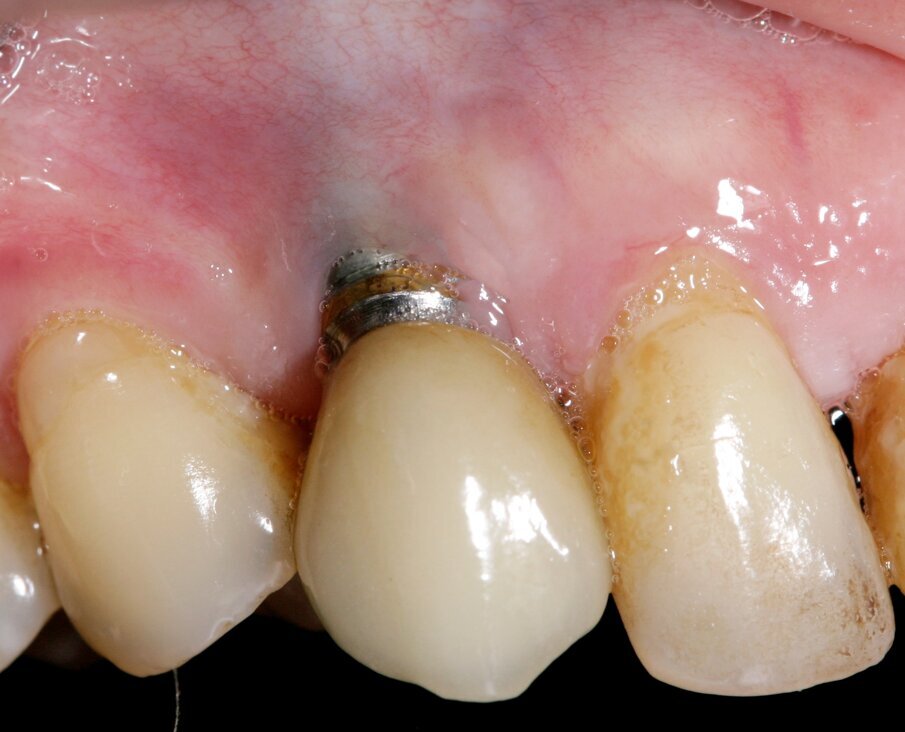

For peri-implant soft tissue, a zone of keratinized tissue is known to provide better long-term stability (Fig. 4). However, from a soft tissue augmentation perspective, either for a tooth or an implant, the buccal positioning is critical when assessing the predictability of the surgical procedure at baseline. The more buccal the implant/tooth, the harder it generally is to graft around (Fig. 5).

Fig. 5. Buccal positioning of a tooth/ implant will negatively impact root coverage , and needs to be carefully assessed.